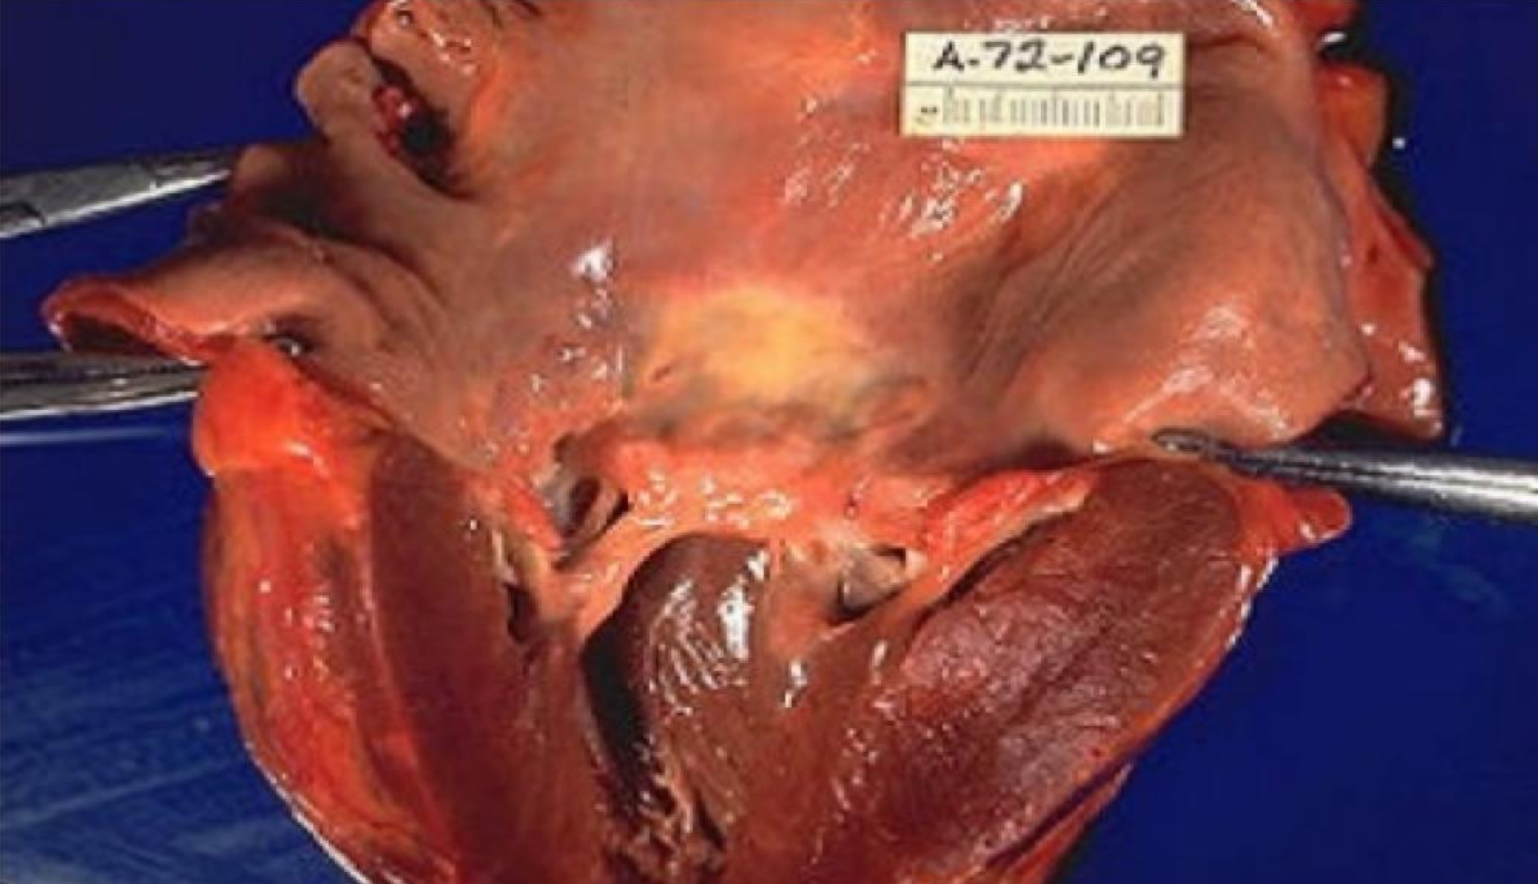

Mitral valve insufficiency + stenosis viewed from left atrial aspect, valve has a narrowed

orifice looks like “Fish mouth”

-affects blood flow on left side of heart